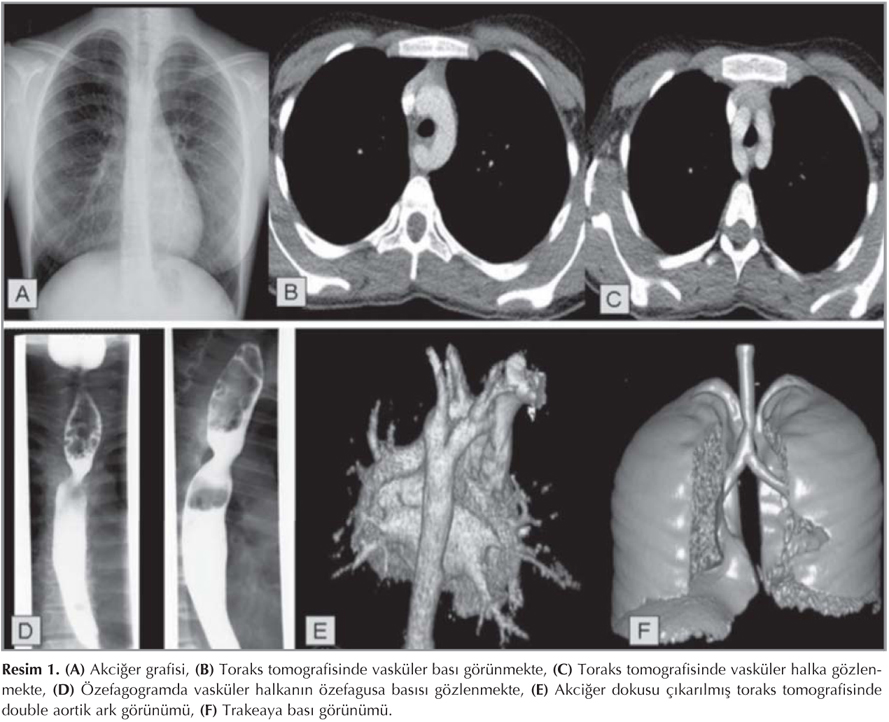

?ekil 1

On be? ya??nda kad?n hasta ate?, balgaml? ?ks?r?k nedeniyle ba?vurdu. Yakla??k 10 g?nd?r nebulize salbutamol ve steroid kulland???, dokuz ya??ndayken ast?m tan?s? alarak iki y?l d?zenli tedavi ald???, 13 ya??ndayken pn?moni nedeniyle yatarak tedavi ald??? ??renildi. Fizik muayenesinde vital bulgular? normal olan hastan?n her iki akci?erinde yayg?n ral ve ronkusleri mevcuttu. Di?er sistemik muayene bulgular? ola?an olan hastan?n tetkiklerinde hemogram parametreleri normal, C-reaktif proteini 5.7 mg/dL saptand?. Di?er biyokimyasal parametreleri normal saptand?. Tekrarlayan akci?er infeksiyonu ?yk?s? olan hastan?n altta yatan nedene y?nelik yap?lan tetkiklerinde imm?nglobulin d?zeyleri, ter testi, ekokardiyografik incelemesi ve ppD testi normal saptand?. Hastan?n akci?er grafisinde mediastende ??pheli g?r?n?m nedeniyle ?ekilen ?zefagus mide duedonum grafisinde aortik ark seviyesinde vask?ler yap?lar?n ?zefagusu yanlardan bas?lad??? saptand?. Bu seviyede ?zefagus pasaj? daralm?? olup transvers ?ap? 7 mm idi. Bilgisayarl? toraks tomografisinde ?ift aortik ark anomalisi g?r?ld? (Resim 1). Tedavileri tamamlanan hastan?n yutma i?levinin d?nem d?nem ?ikayete sebep olmas? ve solunum sistemi yak?nmalar?n?n d?zelmesi nedeniyle takibe al?nd?.

Resim 1

Akci?er grafisinde trakea hava g?lgesine bas? tespit edilmesi vask?ler ringi d???nd?rmelidir (1-3). Tan? i?in baryumlu ?zefagografinin yeterli olmad??? durumlarda anjiyografi veya toraks tomografisi kullan?labilinir (2,5). Olgumuzda akci?er grafisi bulgular? ile ??phelenilmesi ile ?ekilen ?zefagus-mide-duedonum grafisi ve toraks bilgisayarl? tomografide ?ift aortik ark saptanm??t?r.